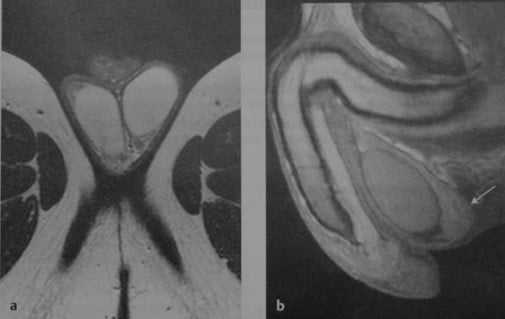

Нормальные яички. МРТ: (а) Аксиальное Т2-взвешенное изображение. Нормальная интенсивность сигнала от яичек; (b) Сагиттальное Т1 -взвешенное изображение после внутривенного введения контрастного вещества. Сигнал средней интенсивности от яичка. Нормальный хвост придатка (стрелка).

Что покажет МРТ при нормальной мошонке

- гомогенный сигнал средней интенсивности на Т1-взвешенном изображении

- Высокая интенсивность сигнала на Т2-взвешенном изображении

- Гипоинтенсивная перегородка идет радиально от капсулы к средостению яичка

- Белочная оболочка: тонкая линия с низкой интенсивностью сигнала

- изоинтенсивный по сравнению с яичками на Т1- взвешенном, гипоинтенсивный на Т2-взвешенном изображении

- более выраженное контрастное усиление по сравнению с яичками.